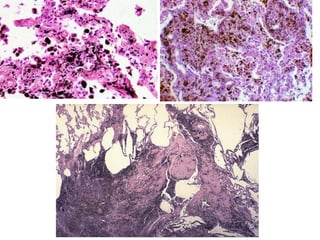

Microscopy

 Asbestos bodies: asbestos fibres coated with a film of proteins

rich in iron.

 Golden brown, fusiform or beaded rods.

 coating is thickest at ends - Dumbell shape

 form when macrophages phagocytose asbestos, iron derived

from phagocyte ferritin.

• Ferrugious bodies : other inorganic

particles/fibres coated with similar protein

iron complex

Pathologic features • Beginin lower lobes and sub pleura • Early stages – minimal fibrosis • Late stages- extensive fibrosis- destroys the architecture-dilated/cystic air spaces- honeycombed appeareance

Microscopy  Asbestos bodies:asbestos fibres coated with a film of proteins rich in iron.  Golden brown, fusiform or beaded rods.  coating is thickest at ends - Dumbell shape  form when macrophages phagocytose asbestos, iron derived from phagocyte ferritin.

• Ferrugious bodies: other inorganic particles/fibres coated with similar protein iron complex